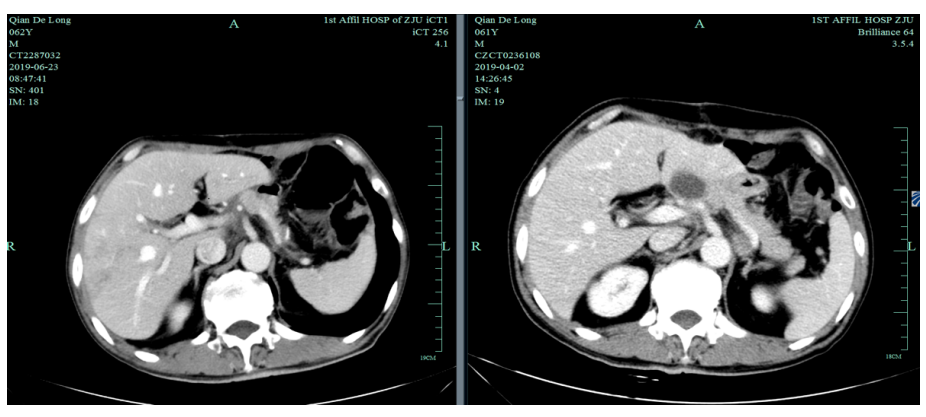

一线化疗疗效评估(2019.6 vs 2019.4):胃癌术后改变。影像评估CR。

由于奥沙利铂8个周期化疗结束,2019-6-26至2019-11-29行S-1+赫赛汀 q3w 8周期联合维持治疗:替吉奥3# BID D1-14、赫赛汀 300mg D1。

影像学评估:胃癌术后改变。持续CR。

2020-11-3全腹部CT平扫+增强提示胃癌术后改变,术周及腹膜后多发肿大淋巴结显示,对照2020-7-7CT淋巴结肿大进展,结合临床疗效评估PD。